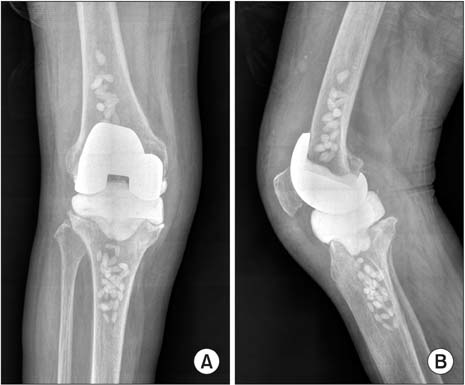

Правила реабилитации после эндопротезирования коленного сустава

Одно из осложнений эндопротезирования — нестабильность в области надколенника из-за неправильной ориентации имплантата.